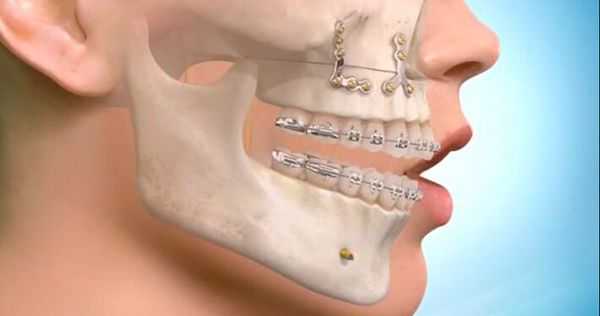

Самым частым методом ортопедического лечения переломов является двучелюстное шинирование — наложение на зубные ряды шин-скоб с репозицией отломков и фиксацией прикуса в привычном для больного положении. Этот метод консервативен и малотравматичен, но в ряде случаев не позволяет получить хорошей фиксации фрагментов верхней челюсти, особенно при высоких и сложных переломах. В среднем при переломах верхней челюсти требуется обездвиживание и ограничение жевательной нагрузки на срок 4-5 недель.

Самым современным и адекватным методом лечения на данный момент является остеосинтез (фиксация титановыми накостными конструкциями) переломов верхней челюсти. Это хирургическое вмешательство, выполняемое из внутриротовых разрезов. При таком варианте лечения можно точно сопоставить и зафиксировать фрагменты для создания условий их сращения [7] .

При лечении высоких переломов также используется коронарный доступ, который позволяет создать косметичный и широкий доступ к костям всей средней зоны лица и глазницам [5] . Своевременное выполнение остеосинтеза позволяет предотвратить поздние послеоперационные осложнения, облегчить реабилитацию пациента и ускорить сроки выздоровления.

Стоит отметить, что очень важно постоянное ношение межчелюстной фиксации для плотного контакта фрагментов и исключения их подвижности, особенно под действием жевательной нагрузки [9] . Также необходимы качественная гигиена полости рта и наблюдение пациента у челюстно-лицевого хирурга